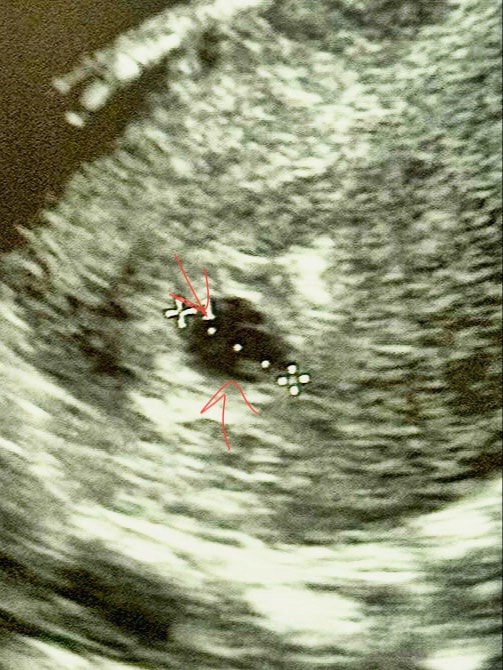

Ангелина, в заключении плодное яйцо 11мм жм 3мм

Если бы было 2 жм то в заключении так и написали бы, указав размеры обоих жм. А поскольку у вас указан 1, то он там 1, не стоит разглядывать эти фотки.

я не вижу два ... думается один